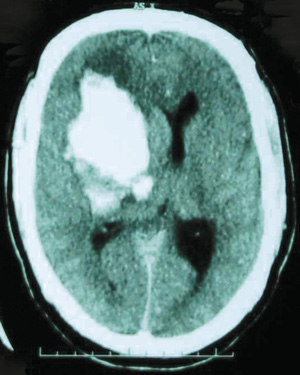

Computed tomography of the brain showed an 8 × 5 × 7 cm haemorrhage centred on the basal ganglia, 1 cm midline shift and right lateral ventricle effacement with subarachnoid extension filling the third and fourth ventricles, a small haemorrhage in the cerebral peduncles and the left caudate nucleus, with blood surrounding the brainstem at the foramen magnum (Box). The haemorrhage was not considered surgically salvageable by the neurosurgeon.